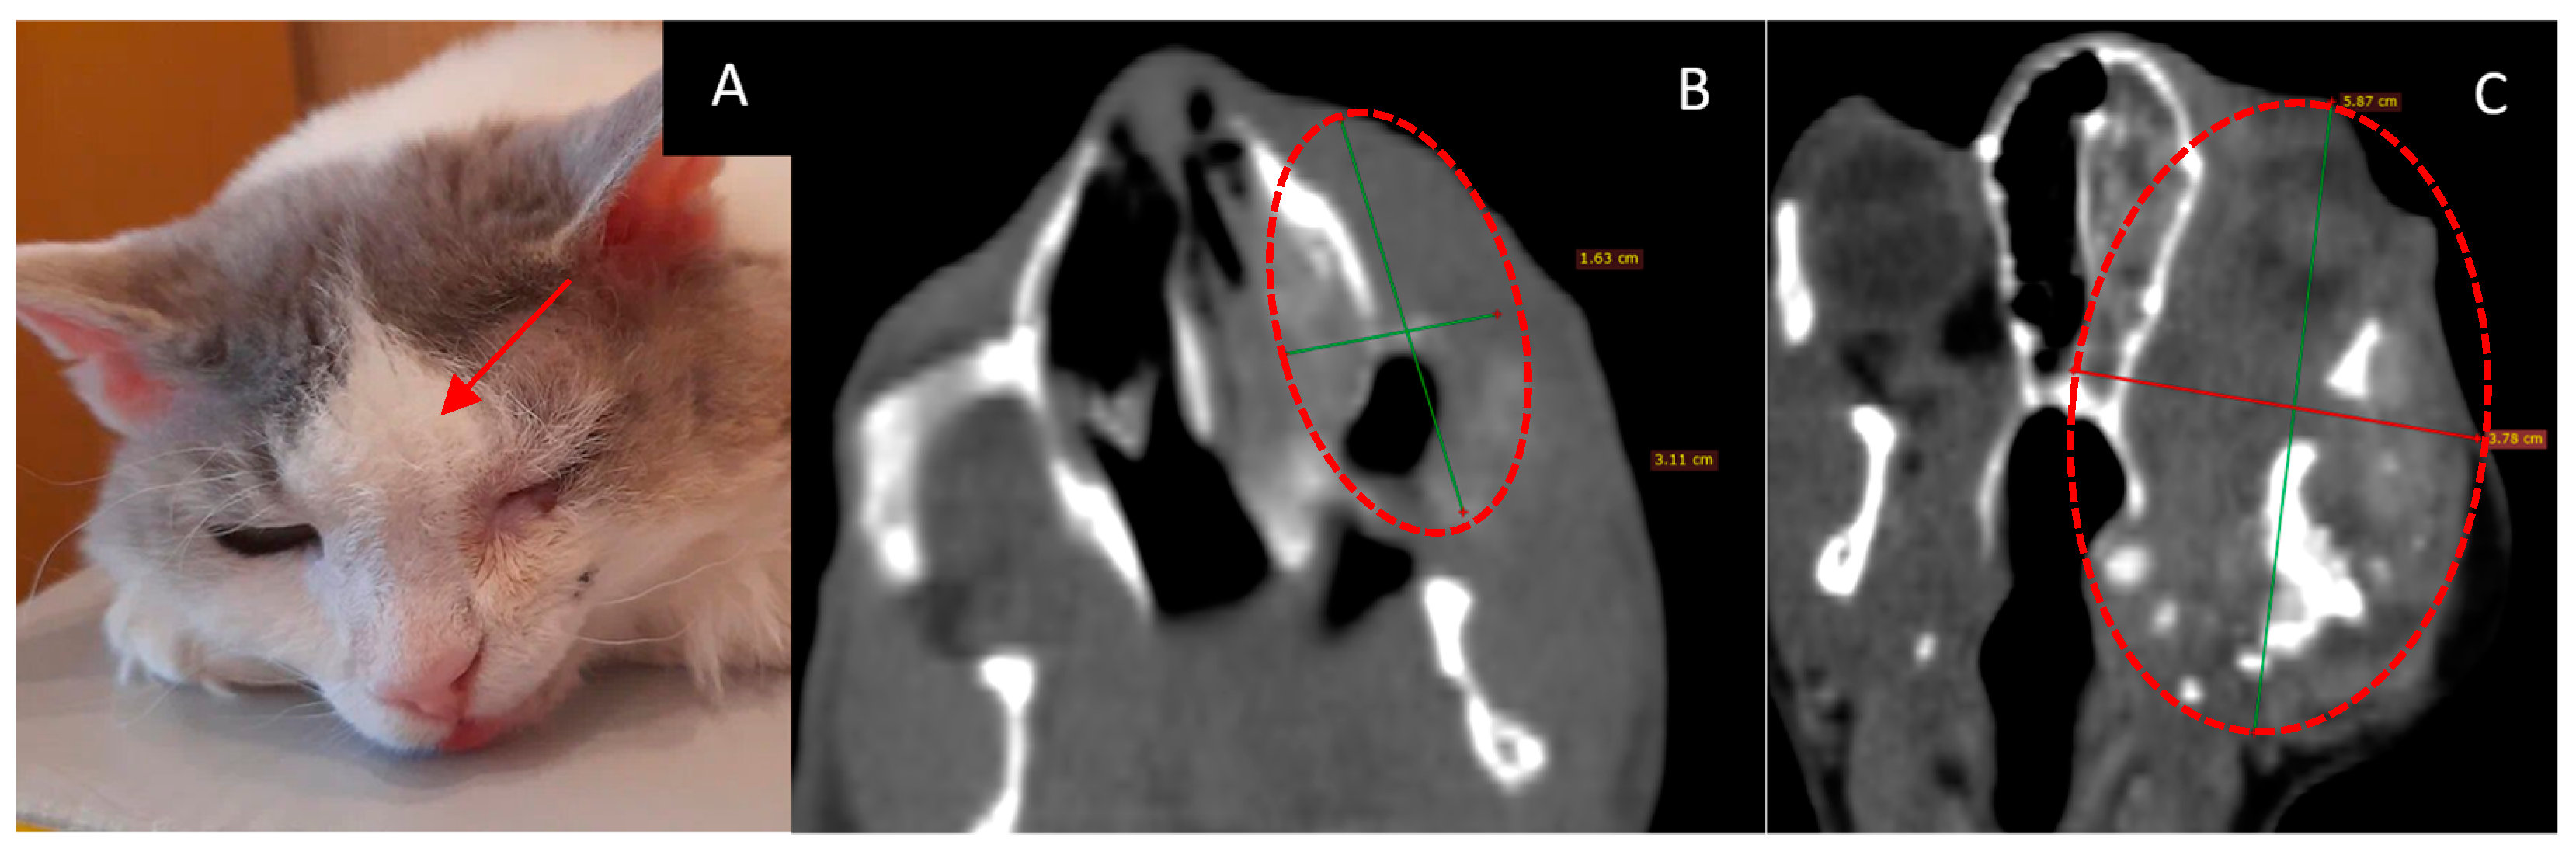

3.1. Female Cat “Ayuta”

- Age: 11 years.

- Symptoms: worsening of nasal breathing and nasal discharge.

- Tumor localization: right nasopharyngeal area. The nasopharyngeal tumor was visualized using CT.

- Treatment other than GdNCT (surgery, radiation, or chemotherapy): none.

- Final pathological diagnosis: highly differentiated adenocarcinoma of the nasal mucosa.

- The course of the disease after GdNCT: during follow-up, the overall condition was satisfactory, and nasal breathing improved. At the examination, the visible part of the tumor decreased in size. A CT scan performed 3 months after GdNCT revealed no significant changes compared to the pretreatment visualization (Figure 1).